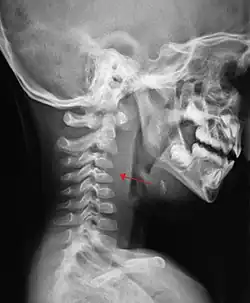

A lateral cervical spine X-ray demonstrating prevertebral soft tissue swelling (marked by the arrow) as seen in a person with a retropharyngeal abscess

X-ray of the neck often (80% of the time) shows swelling of the retropharyngeal space in affected individuals. If the retropharyngeal space is more than half of the size of the C2 vertebra, it may indicate retropharyngeal abscess.[5]